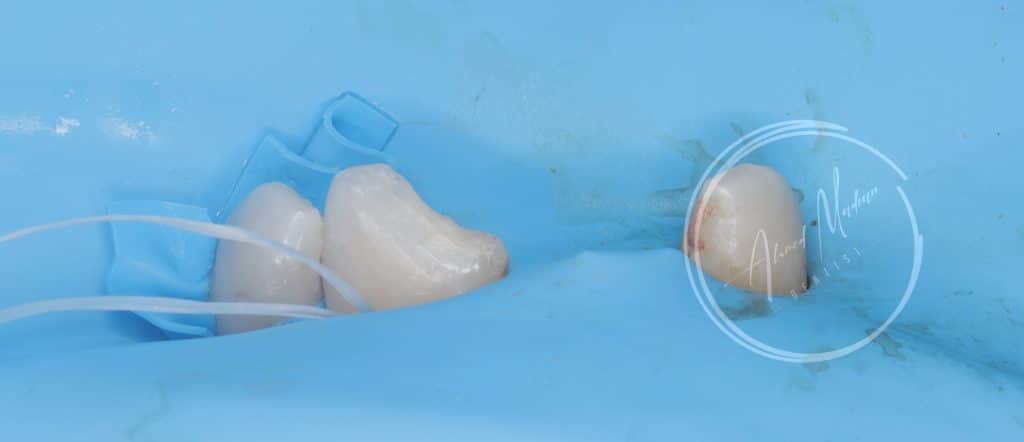

Ttt plan :-

11 – gingivectomy , DME , build up , cleaning and shaping , intra canal medication and patient will be under follow up for the next month considering the initiation of internal or external resorption , after follow up RCT , fiber post will be placed

12 – direct composite restoration